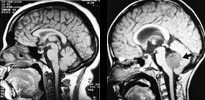

MR-teknikken har hatt stor betydning for barn med medfødte misdannelser (21). Spesielt gjelder det barn med myelomeningocele og migrasjonforstyrrelser i hjernen. I moderne behandling av hydrocephalus er de nye MR-teknikkene av stor betydning både før og etter nevrokirurgiske inngrep. Det er gunstig at det ved MR-diagnostikken ikke brukes ioniserende røntgenstråler. Disse barna ville ellers måtte utsettes for relativt store stråledoser gjennom et langt liv med CT-kontroller (22).